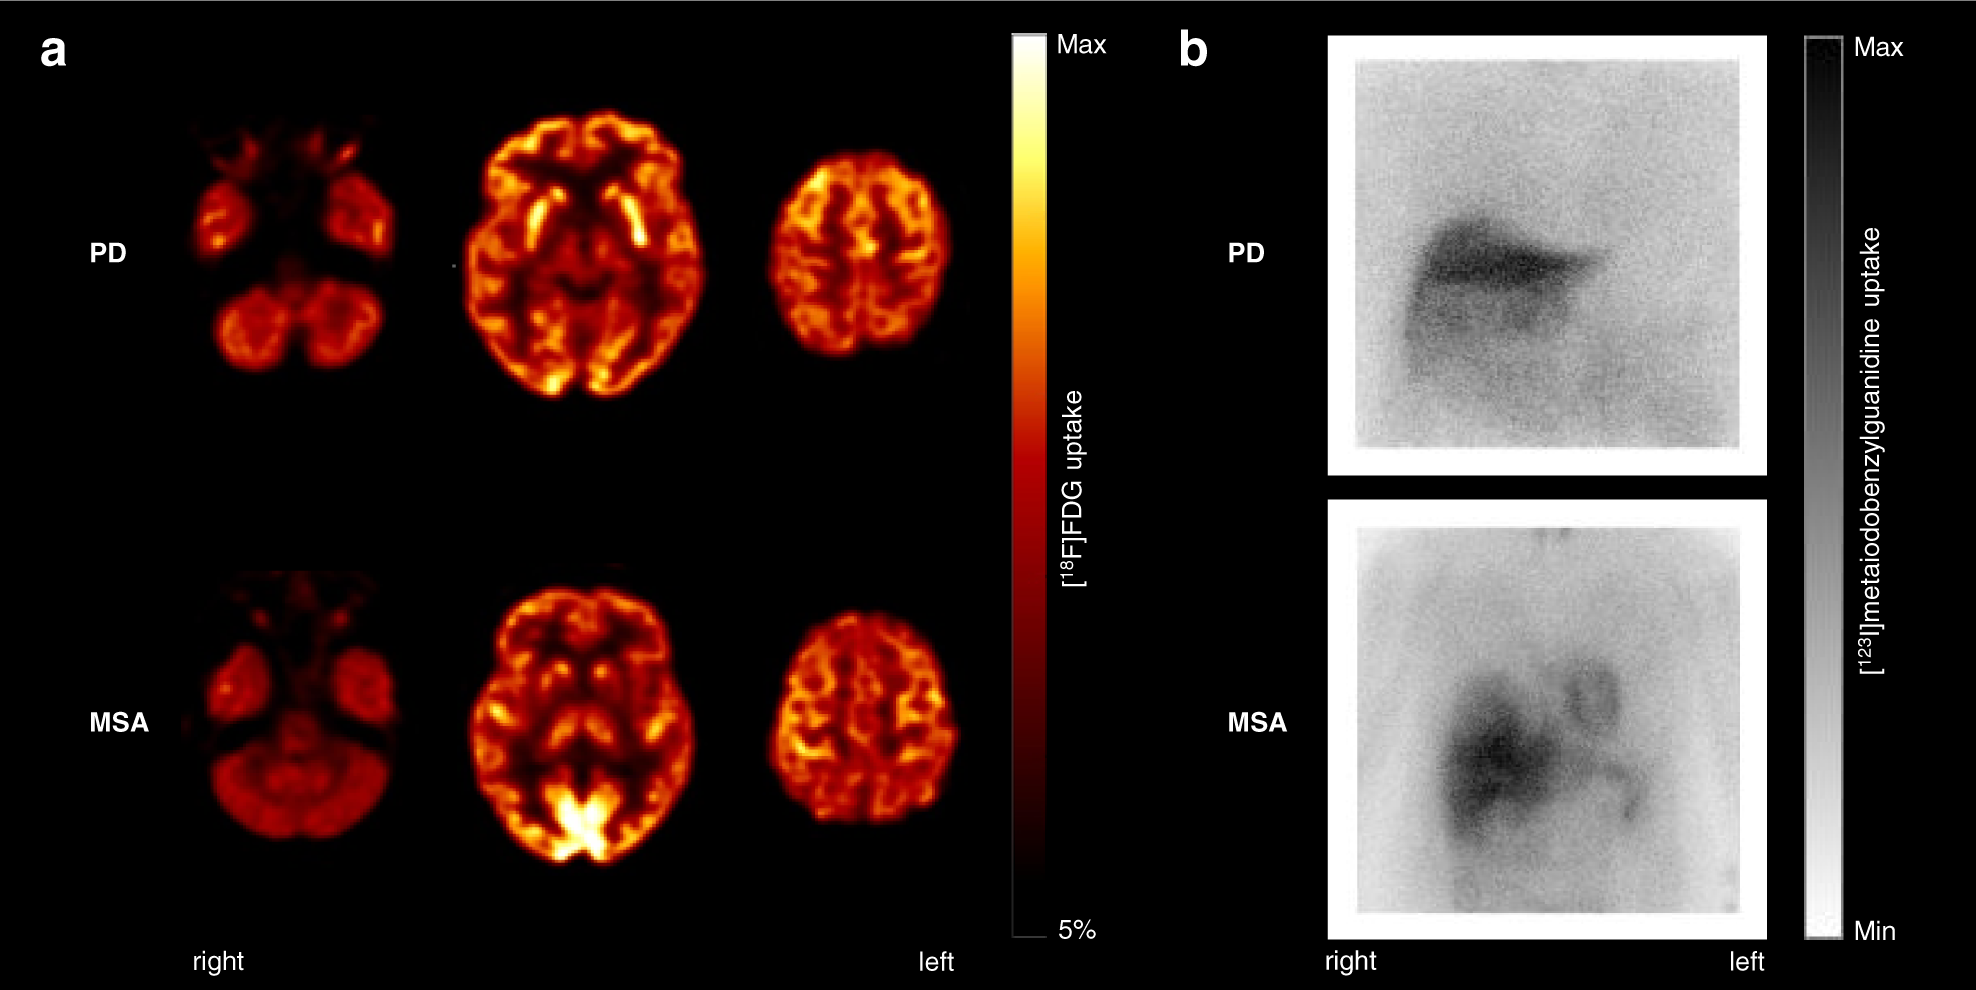

Fig. 3: Typical FDG PET and MIBG scintigraphy findings in individual patients with Parkinson’s disease and multiple system atrophy.

a Spatially normalized transaxial FDG PET slices at the level of cerebellum, basal ganglia, and dorsal frontoparietal cortex. Datasets were thresholded for optimal display. b Anterior view of planar MIBG scintigraphy. The patient with PD shows a typical relative hypermetabolism of the bilateral putamen and no cardiac MIBG uptake. The MSA patient is characterized by hypometabolism of the putamen (particularly on the left side), the bilateral cerebellum, and a preserved cardiac uptake on MIBG scintigraphy. PD Parkinson’s disease, MSA multiple system atrophy.